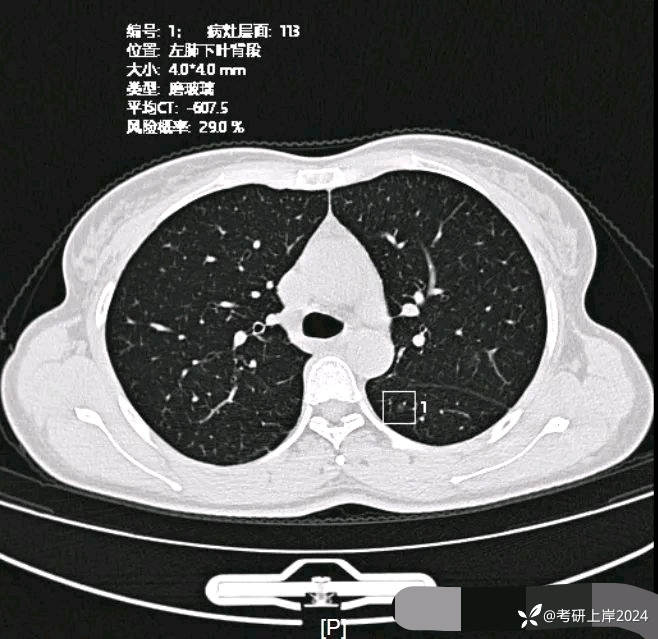

患者最近的检查有AI辅助诊断意见,找出的病灶分别如下:

病灶13:左下叶微小磨玻璃结节,边缘欠清,病灶过小,考虑少许纤维增生或肺泡上皮增生可能性较大;

病灶18:左下叶极淡密度结节,但轮廓却清,考虑肺泡上皮增生可能性大;